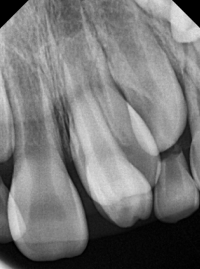

과잉치는 발생 위치와 형태에 따라 여러 종류로 분류됩니다.

일반적으로 과잉치는 맹출 부위, 모양, 그리고 발생하는 시기에 따라 분류할 수 있습니다.

-상악 구치 : 상악 소구치나 대구치부위에 추가로 생기는 치아입니다.